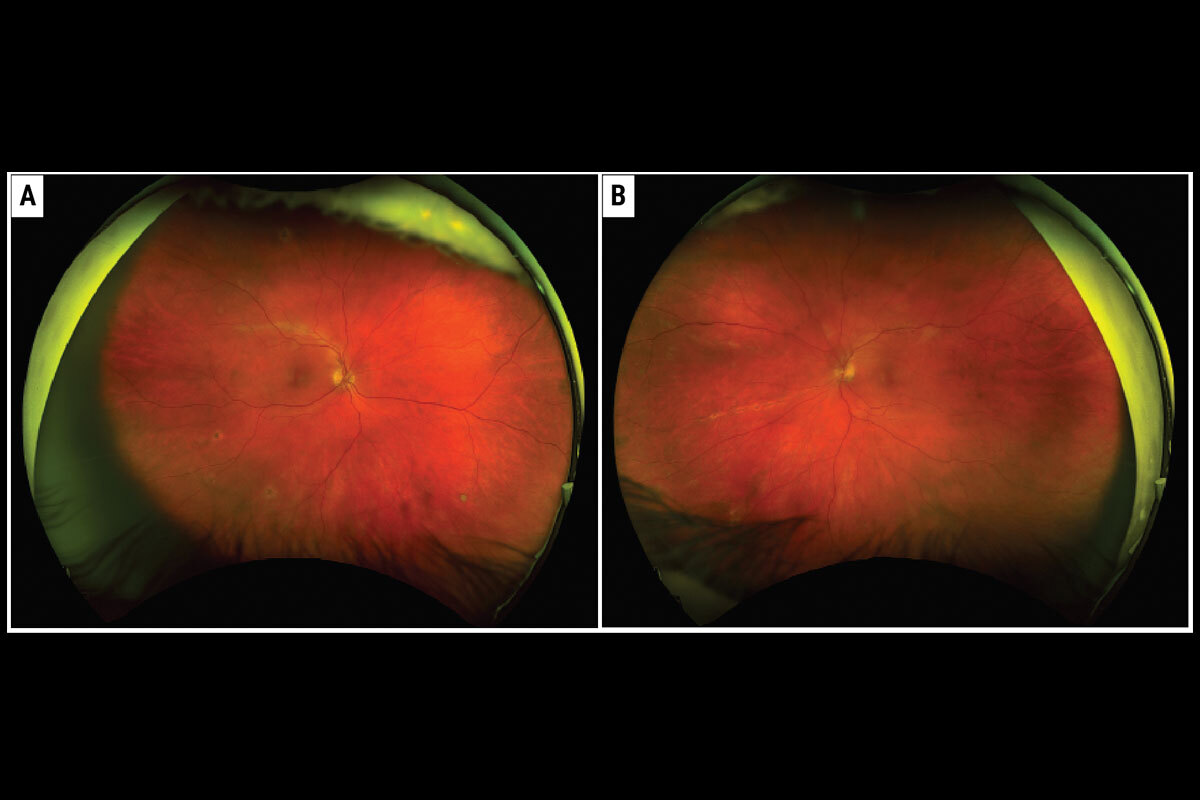

| Figura 2. Este paciente presentó PDR en ambos ojos, lo que se muestra en las imágenes del fondo de ojo preoperatoria tomadas en abril de 2017 (columna de la izquierda). Después del tratamiento con anti-VEGF, la PDR ya no aparece en las imágenes del fondo de ojo un mes después (columna de la derecha). Foto: Jennifer I. Lim, MD. |